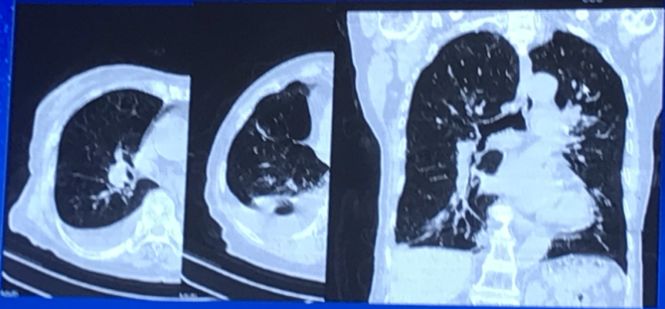

病例二:患者男,79岁。阵发性呼吸困难3年,2周内加重。超声提示存在严重主动脉瓣狭窄以及主动脉瓣反流,NYHA Ⅳ级。存在HTN、DM、COPD以及CKD stage Ⅲ并发症。STS:13.3%,Log EuroScore:35.3%,心脏团队建议行TAVR,CTA结果见Figure 3。

Figure 3

CTA结果